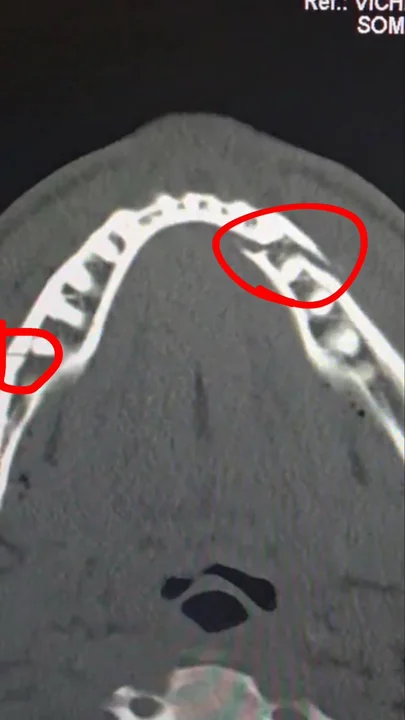

Luego posteó una imagen de la radiografía de su mandíbula, donde se observan las fuertes lesiones que produjeron los golpes de Joshua: "Doble rotura de mandíbula. Dame a Canelo en 10 días"

Paul, por su parte, compartió información en sus redes sociales sobre su estado de salud: "Mandíbula rota. Corazón y huevos intactos. Hora de descansar, recuperarse y volver al peso crucero".